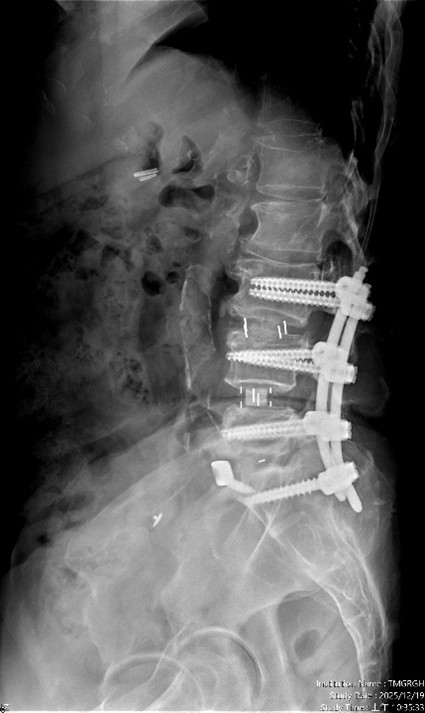

經 臺中市立老人復健綜合醫院 骨科部副部長 林琮凱 醫師 詳細檢查後,診斷為第三、四、五腰椎合併第一薦椎之多節段脊椎狹窄與神經壓迫。醫療團隊與病患及家屬充分溝通後,決定採用「電腦 3D 導航輔助之前位/前側位脊椎融合手術」,合併後方骨釘固定,一次完成多節段重建。術後病患神經症狀明顯改善,行走能力恢復,生活品質大幅提升。

【手術前及手術後】手術前有脊椎滑脫不穩定及脊椎狹窄造成神經壓迫(左圖)。手術後除了重建椎間高度,也將腰椎的生理曲線重建為較理想的前凸狀態(右圖)。官方提供